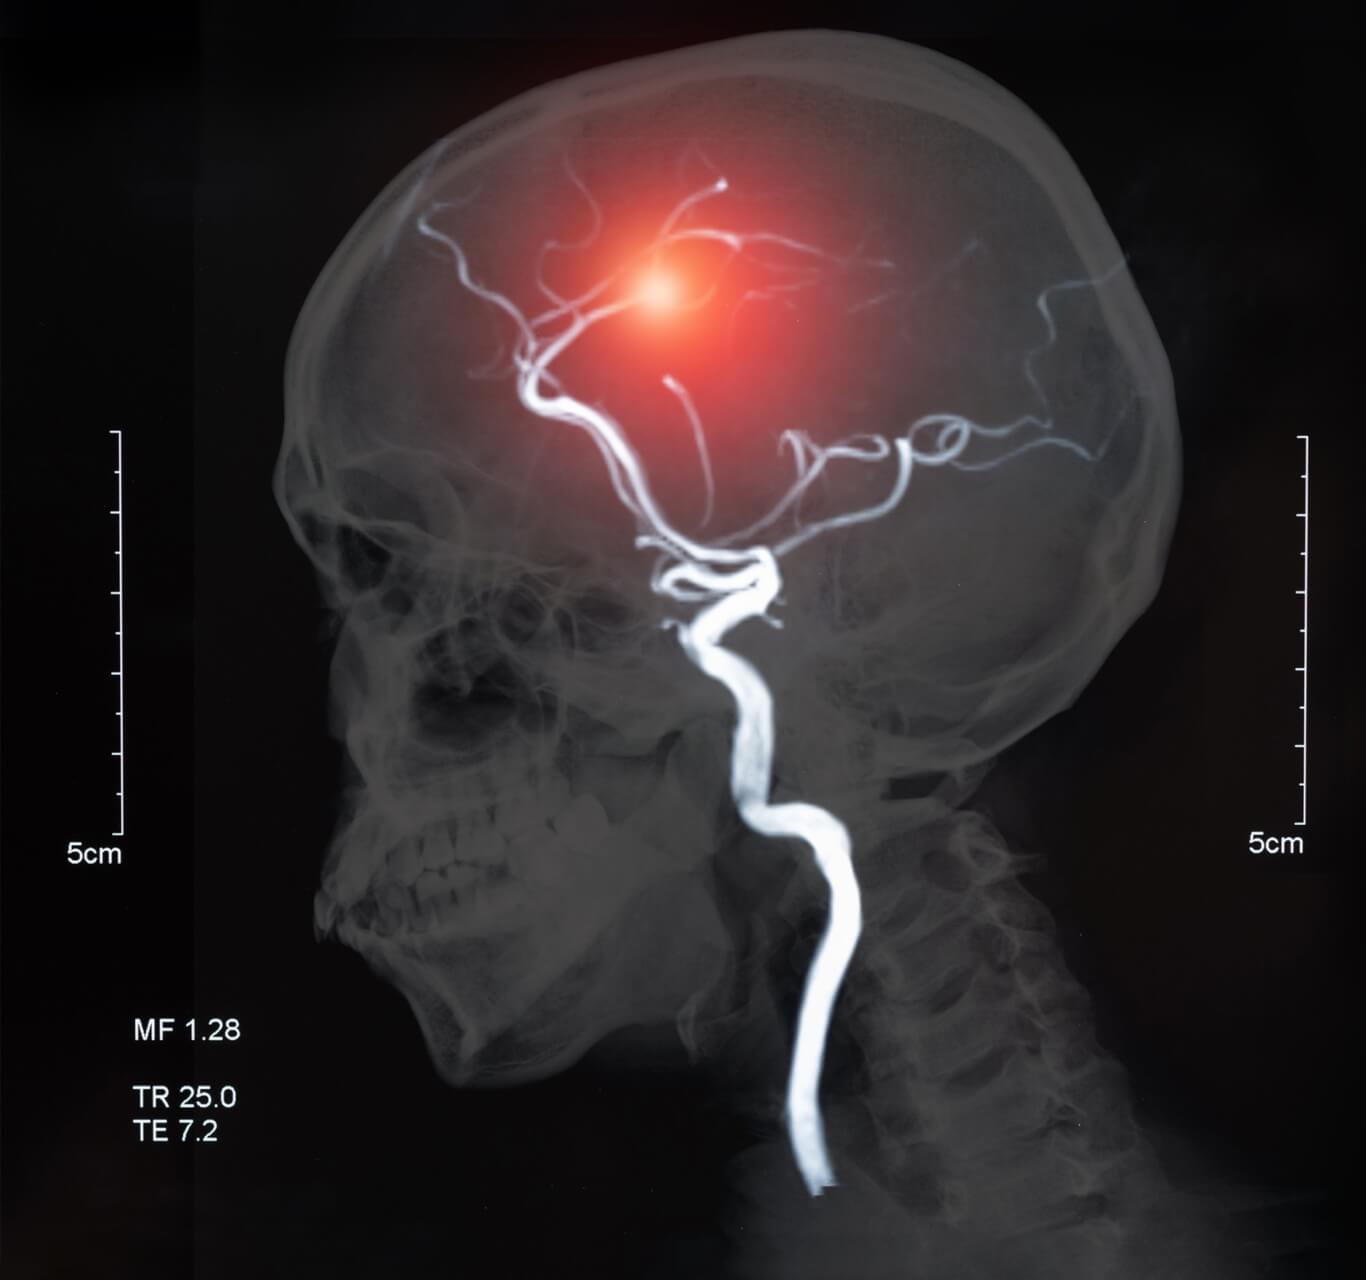

Ein Schlaganfall, der auch als Hirninfarkt bezeichnet wird, ist in fünf von sechs Situationen die Folge eines Gefässverschlusses. Dabei verstopft ein Blutgerinsel ein Blutgefäss im Hirn. Häufig ist ein Gefäss betroffen, welches aufgrund von Ablagerungen verengt ist. Je nach Grösse des Gefässes und betroffener Region im Gehirn variieren die Symptome und Folgen.

Die andere Ursache ist eine Hirnblutung. Dabei wird ein Gefäss im Gehirn verletzt (zum Beispiel durch einen Unfall und daraus resultierendem Schädel-Hirn-Trauma oder durch ein geplatztes Aneurysma), wodurch sich austretendes Blut ansammelt. Je nach Situation staut sich dieses Blut im Gehirn oder zwischen Gehirn und Schädel an, wobei Druck auf das Gewebe ausgeübt wird. Durch den Druck werden die feinen Kapillaren, die Sauerstoff im Gehirn verteilen sollen, beeinträchtigt. Dadurch können sie nicht mehr genügend Sauerstoff transportieren. Auch hier sind die Folgen davon abhängig, welche Region im Kopf betroffen ist.